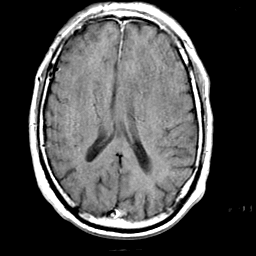

Meningioma, MR Study #1 -- Slice #12

[Home][Help][Clinical] Slice 12